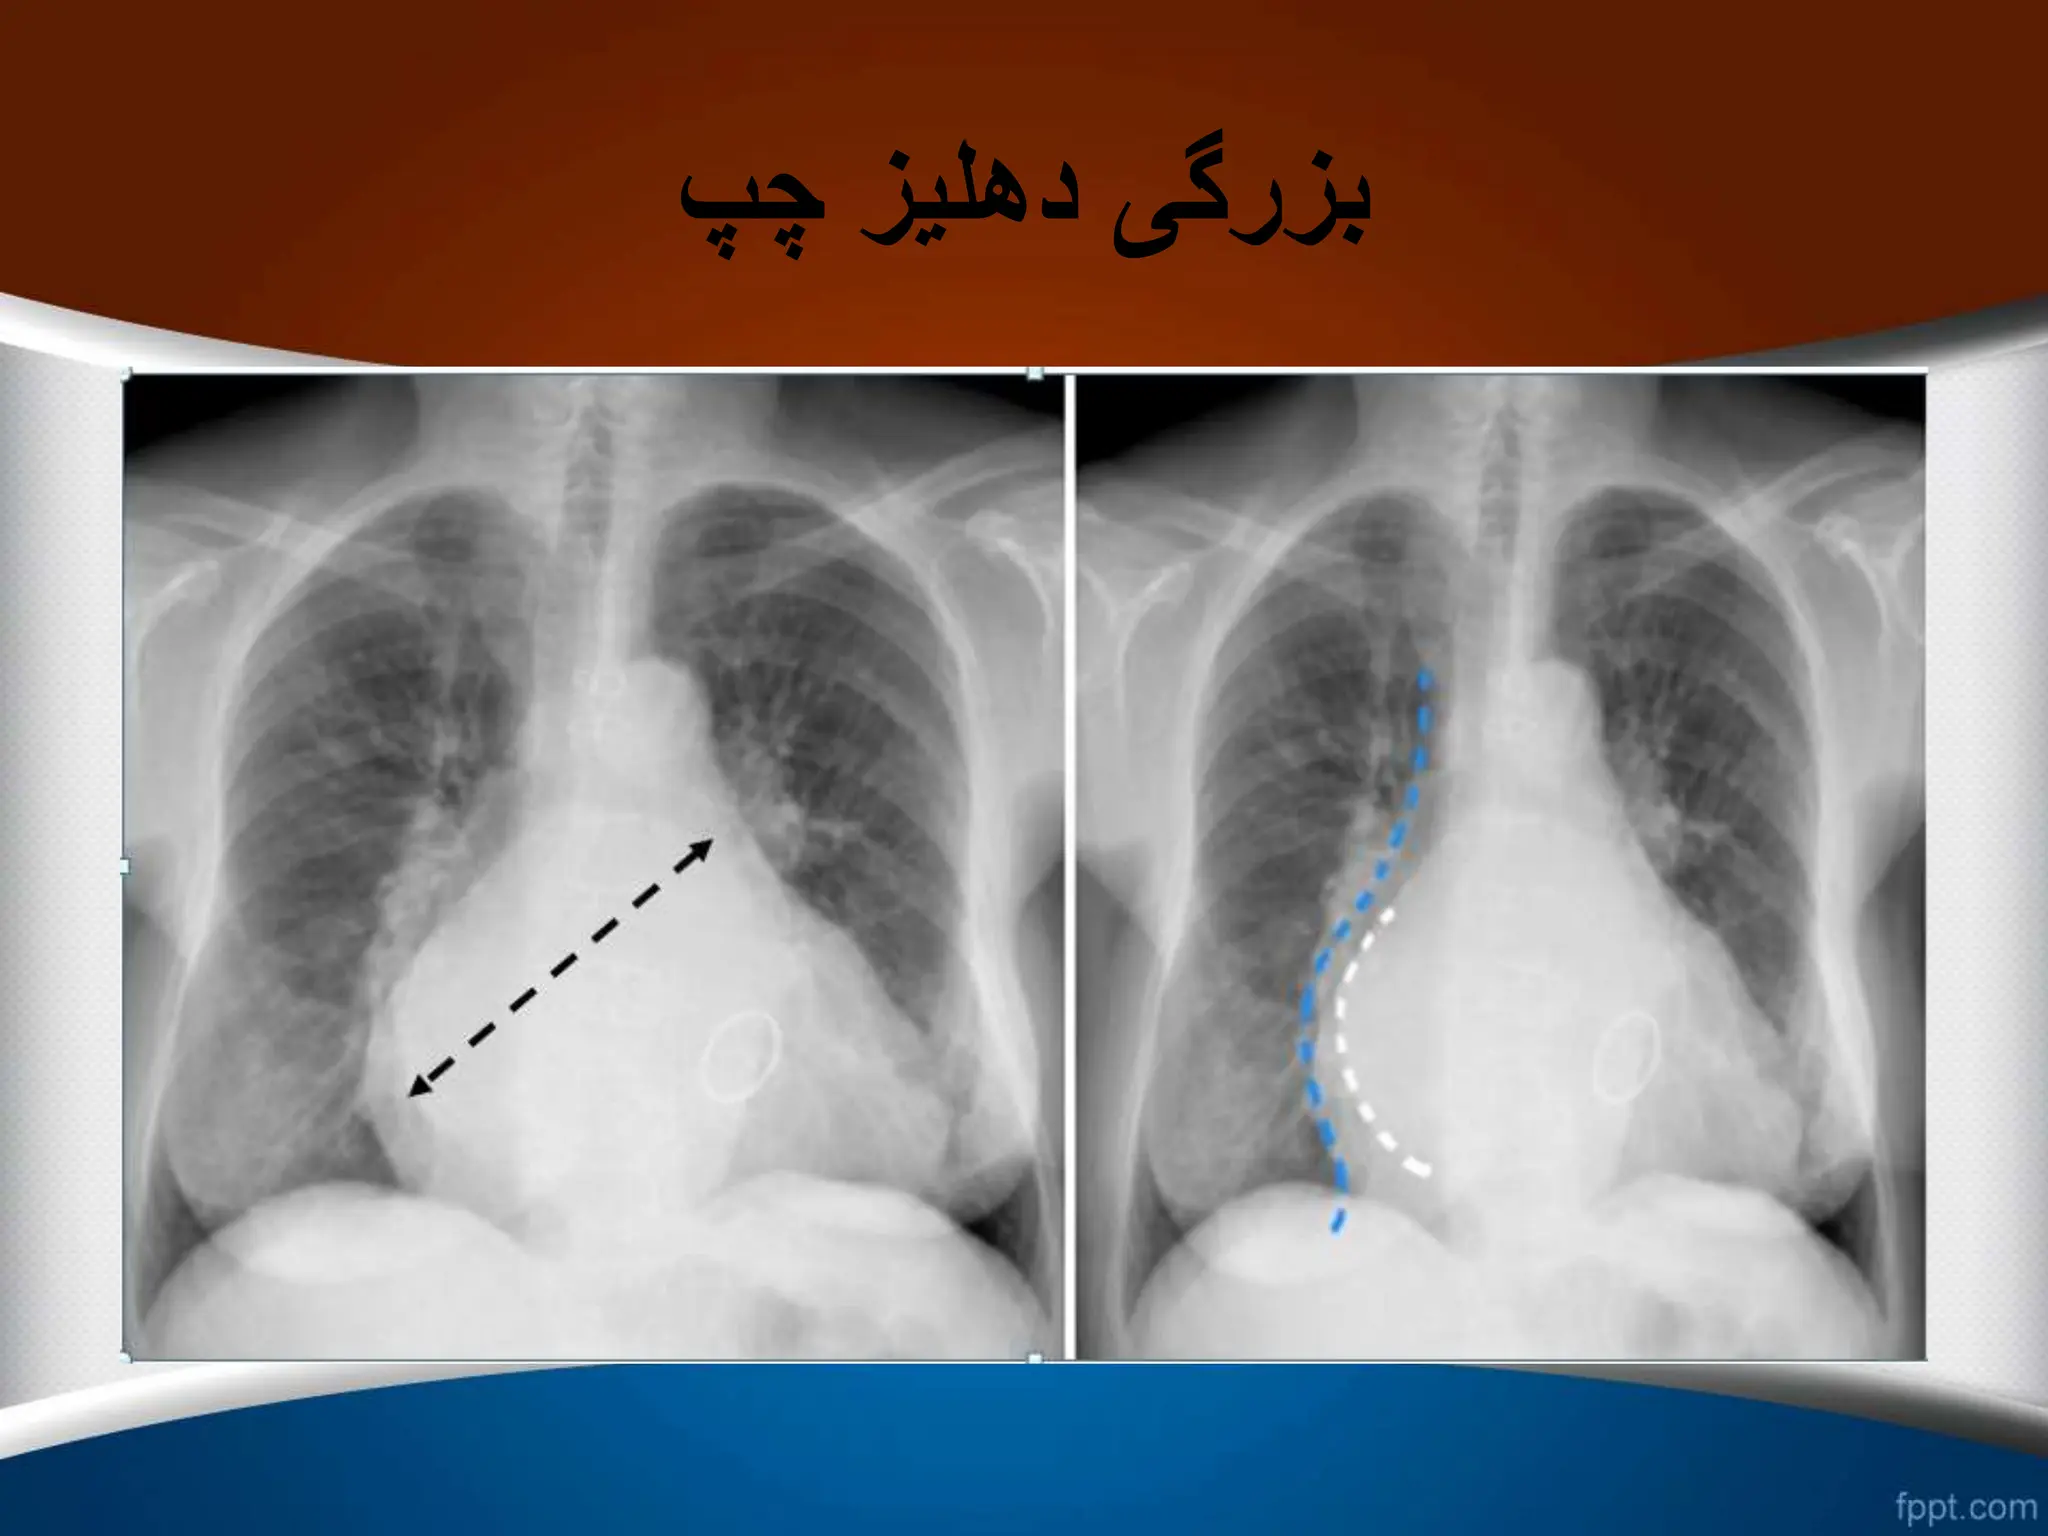

‫چپ‬ ‫دهلیز‬ ‫بزرگی‬